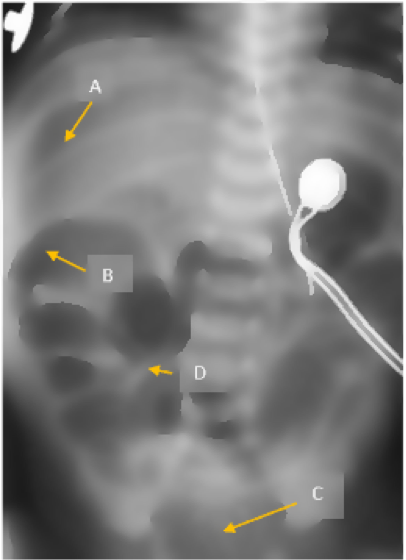

The abdominal x-ray below belongs to a premature neonate with a distended and firm abdomen as well as bilious emesis. Which marker indicates the patient has experienced intestinal perforation? Select the appropriate area.

The correct answer is A. This x-ray demonstrates free air near the liver, something you would only see with a bowel perforation. Options B, C, and D are all pointing to areas within the digestive tract. They may not look quite normal but do not by themselves suggest that a perforation is present.